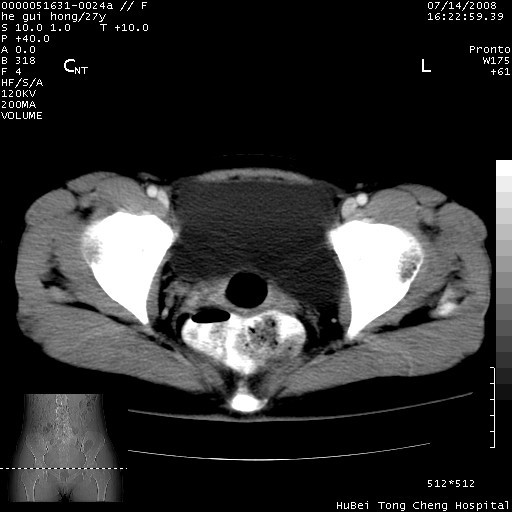

以下是引用杀毒软件在2008-7-20 8:03:00的发言:[br]支持双侧卵巢囊腺瘤可能性大!

以下是引用zjzjr在2008-7-20 13:36:00的发言:[br]双侧附件囊腺瘤可能性大!